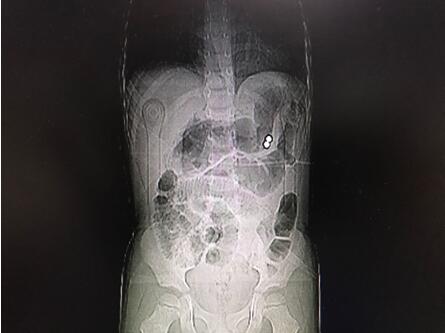

通訊員唐水平報(bào)道:近日,市中心醫(yī)院華新普外科收治了一位4歲的腹痛患兒,進(jìn)院后檢查發(fā)現(xiàn)腹腔內(nèi)有金屬異物及膈下游離氣體、腹腔積液,診斷為消化道穿孔并彌漫性腹膜炎。

據(jù)患兒監(jiān)護(hù)人講述,患兒平時(shí)喜好磁力玩具,發(fā)病前兩天曾先后誤兩顆服彩色磁力珠。由于磁力珠在胃腸道蠕動(dòng)下移到不同部位,因其強(qiáng)大的吸力使間隔胃腸壁及橫結(jié)腸系膜相吸在一起,造成局部組織缺血,繼而壞死穿孔的嚴(yán)重后果。

經(jīng)手術(shù)探查發(fā)現(xiàn)胃體近大彎側(cè)、曲式韌帶下方8cm處空腸及橫結(jié)腸系膜各有一0.5cm大小穿孔,在胃穿孔處的胃腔內(nèi)外各發(fā)現(xiàn)一彩色磁力珠。經(jīng)修補(bǔ)胃腸道穿孔及抗感染、補(bǔ)液治療,患兒術(shù)后順利康復(fù)院。